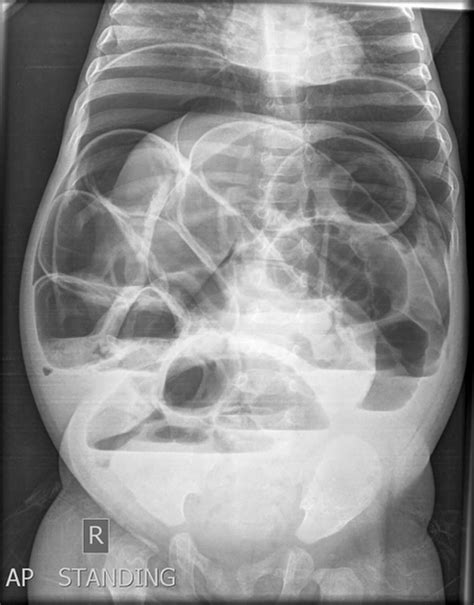

Strict adherence to the surveillance schedule set by your medical team is vital. This often includes regular colonoscopies, imaging tests (such as CT scans), and blood tests to monitor tumor markers. These screenings are designed to detect any potential issues, such as the return of polyps or cancer, at the earliest possible stage, when they are most treatable.